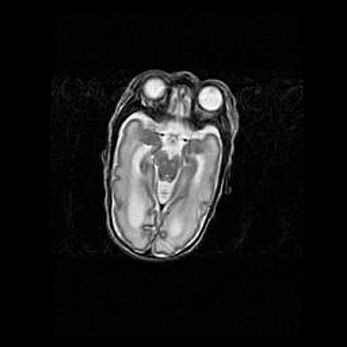

Сообщающаяся гидроцефалия. Кистозная энцефаломаляция головного мозга.

Возраст: 3 месяца 4 дня

Вес: 3100 г

Пол: женский

Окружность головы: 34 см

Срок гестации: 31 неделя

Кистозная энцефаломаляция головного мозга - одна из форм поражения головного мозга в детском возрасте. Характеризуется возникновением множественных и распространённых кист в коре, белом веществе и подкорковых образованиях головного мозга у плодов, новорождённых и детей раннего возраста. Развитие кистозной энцефаломаляции связано с внутриутробной асфиксией и гипотонией, родовой травмой, тромбозом синусов, пороками развития сосудов, инфекциями, сепсисом и другими причинами. Наиболее значимые инфекционные агенты: вирусы простого герпеса, цитомегалии, краснухи, токсоплазмы, энтеробактерии, золотистый стафилококк и другие.